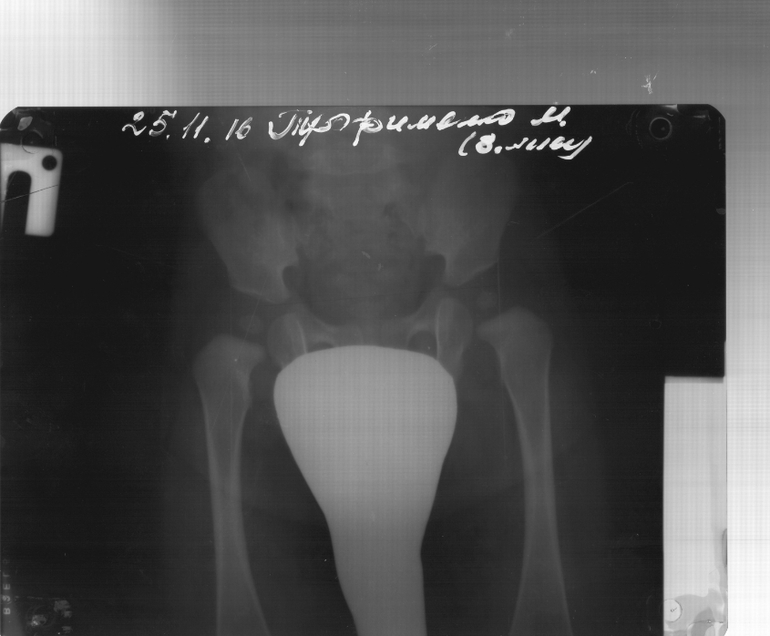

Около месяца у сыночка обнаружили подозрение на Дисплазию,делали узи левый и правый сустав тип 2,незрелость ТБС(((приписали стремена,но я так ине смогла заставить ребенка в них находиться,доходило до ужасных истерик,делали только массаж((((в 3 месяца после рентгена ее исключили,сказали все нормально,нужно суставам окостенеть,и это не страшно,до 6 месяцев все будет отлично!В пятницу (нам почти 8 м),были на приеме у ортопеда после снимка поставили диагноз"Врожденная двухсторонняя дисплазия"((Это как понимать стать хуже не должно было!!!он пополз в 5 месяцев, сам встал с опорой в 6 месяцев и сразу начал ходит с опорой, и сказали засунуть в стремена или подушка Фрейка.Я в растерянности что делать?Фото рентгена 3 месяца и 8 месяцев.